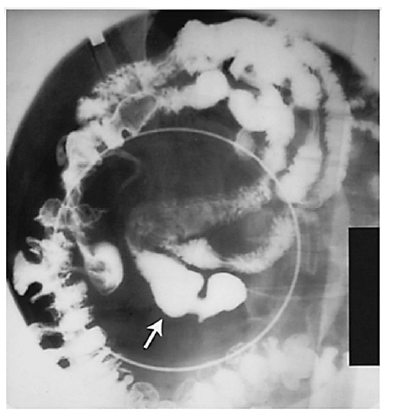

Um paciente do sexo masculino, de 38 anos de idade, assintomático, chega ao consultório médico de um cirurgião em razão de uma alteração em exame de imagem. O paciente é previamente hígido. Refere praticar atividade física, que consiste em corridas e academia quatro vezes por semana, no total. Nega uso contínuo de medicações, tabagismo, alcoolismo e uso de drogas. Além disso, relata não ter tido alergias medicamentosas nem ter feito cirurgias prévias. Nega dor abdominal, náuseas, vômitos e outros sintomas. Declara não ter ocorrido emagrecimento recente. Ao exame físico, o paciente está em bom estado geral, lúcido e orientado. Os resultados de seus exames são: PA = 120 mmHg x 80 mmHg, FC = 80 bpm, Sat. de 98% em ar ambiente. Abdome: flácido, depressível, indolor. Sem massas palpáveis ou visceromegalias. O exame alterado foi de raios X de abdome com contraste baritado, que está representado na figura.